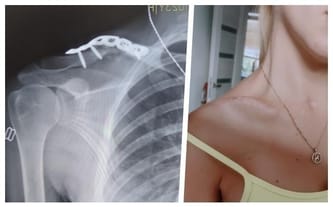

Paulina wypadła z 6 piętra❗️ Pomóż jej wrócić do sprawności!

Cel zbiórki: Intensywna rehabilitacja, dojazdy, zabieg usunięcia blizn, leczenie, wizyty

Stan po wypadku - upadek z wysokości